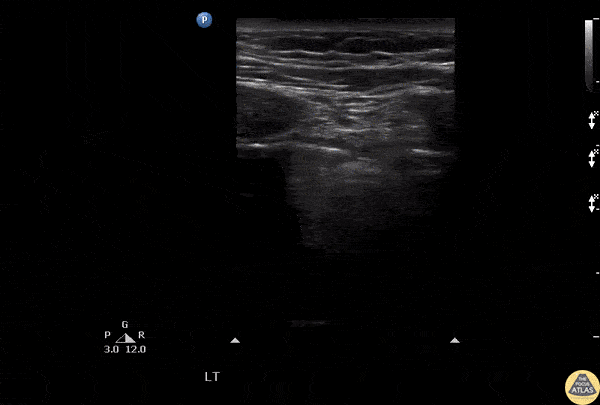

Lung ultrasound reveals absent lung sliding with intermittent lung pulse seen. These findings are consistent with pneumothorax. Image courtesy of Robert Jones DO, FACEP @RJonesSonoEM Director, Emergency Ultrasound; MetroHealth Medical Center; Professor, Case Western Reserve Medical School, Cleveland, OH View his original post here